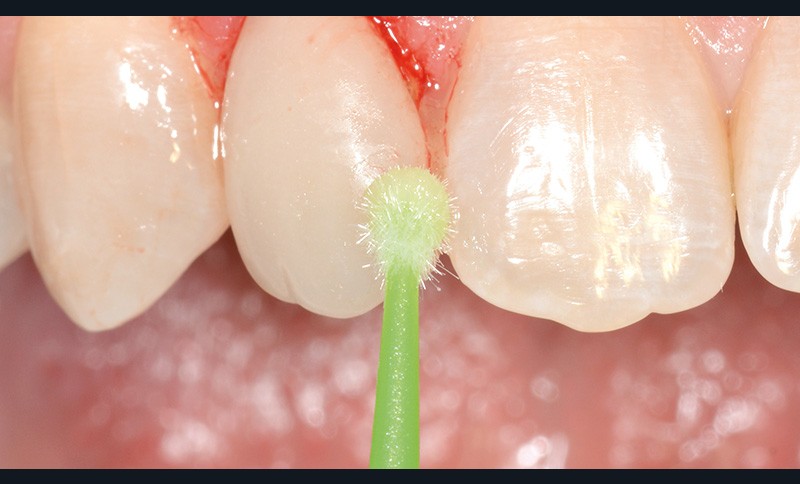

bibli/1.2.11.jpgUne brosse et une ponce sont appliquées afin d’éliminer tous les résidus extrinsèques.

bibli/1.11.jpgNettoyage, surfaçage et polissage parfait des surfaces dures.

bibli/1.2.11.jpgUne brosse et une ponce sont appliquées afin d’éliminer tous les résidus extrinsèques.